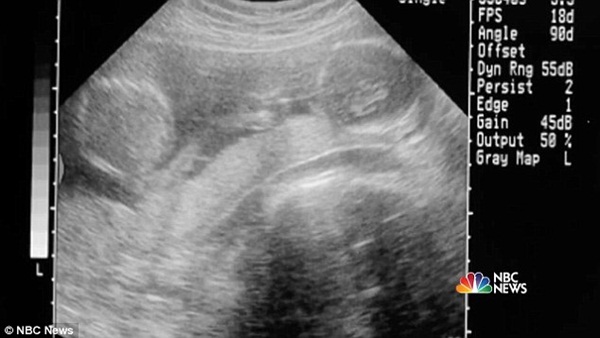

Thế nhưng chưa kịp tận hưởng niềm hạnh phúc to lớn thì Emily và chồng, anh James Stark, đã phải đón nhận tin dữ khi hay tin 2 bé gái trong bụng Emily bị dính liền thân do một trong hiện tượng hiếm, chỉ xảy ra với tỉ lệ chỉ 1/50.000 hoặc 1/200.000.

Mặc dù thuật ngữ "cặp song sinh dính liền" là điều mà cả 2 vợ chồng đều hiểu ngay lập tức nhưng họ không thể ngờ là có một thực tế rằng chỉ có khoảng 35% cặp song sinh dính liền sống sót được hơn 1 ngày sau sinh. Dẫu biết rằng tương lai phía trước không mấy khả quan, James và Emily vẫn quyết tâm làm hết sức mình với hy vọng sẽ giữ các con ở lại với đời và điều mà họ có thể làm trước tiên là suy nghĩ thật tích cực.